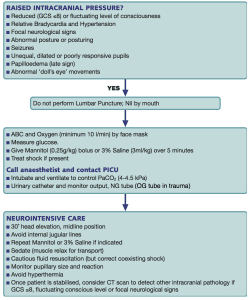

late sign of increased intracranial pressure